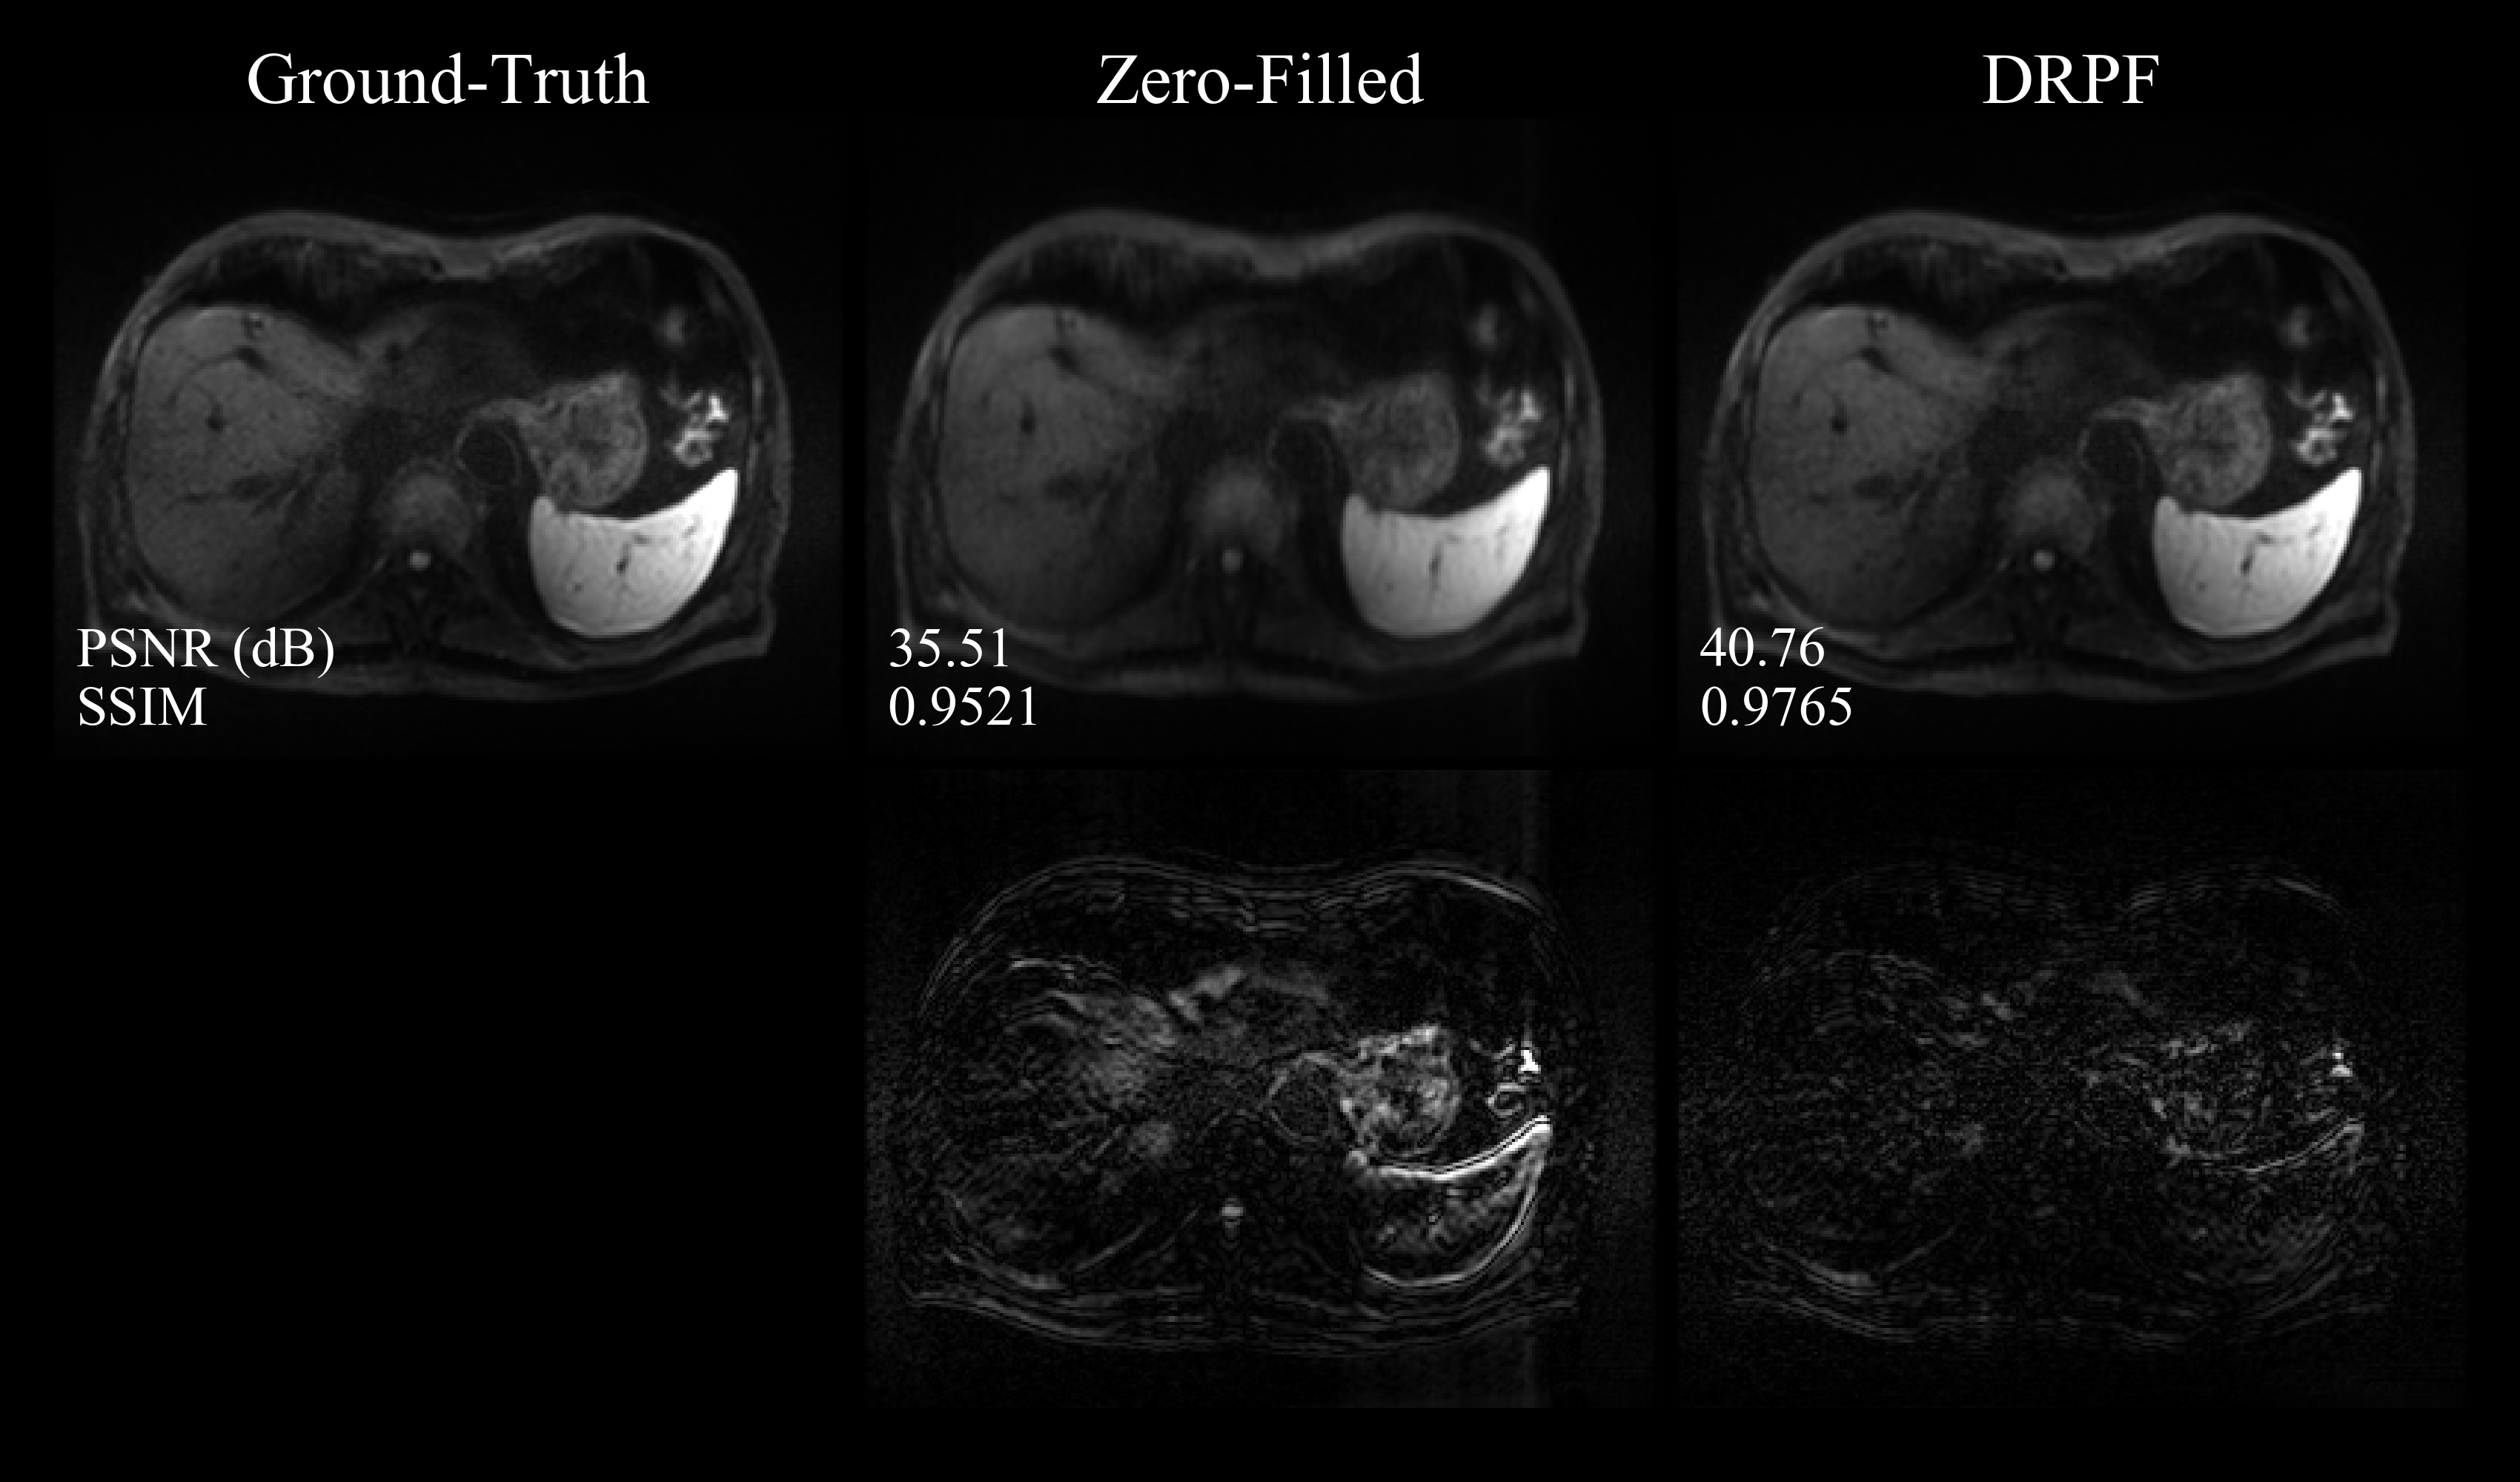

The quantitative evaluation on the whole test set shown in Figure 4 substantiates the findings from the qualitative comparisons. DRPF produces results that are significantly superior to POCS and zero-filling across both PFFs and b𝑏b-values. For a PFF of 5/8 and averaged across both b𝑏b-values, DRPF outperforms POCS by 4.64 dB and 0.0248 in terms of PSNR and SSIM, respectively. Since phase variations become more aggressive with stronger diffusion encoding, POCS tends to introduce more severe artifacts. Consequently, on images acquired at a b𝑏b-value of 800​s/mm2800superscripts/mm2800\,\text{s/mm}^{2}, POCS produces even lower SSIM scores than zero-filling for PFF = 6/8 and outperforms zero-filling only slightly while having a larger variance for PFF = 5/8.

Refer to caption

Figure 4: Quantitative evaluation of zero-filling, POCS and DRPF on the retrospectively PF-sampled test set with respect to two metrics (PSNR: first row, SSIM: second row) as well as two PFFs (5/8: first column, 6/8: second column). Boxes show interquartile ranges while the solid lines within each box represent the median. Whiskers cover up to 1.5 times the interquartile range while circles represent outliers beyond that.